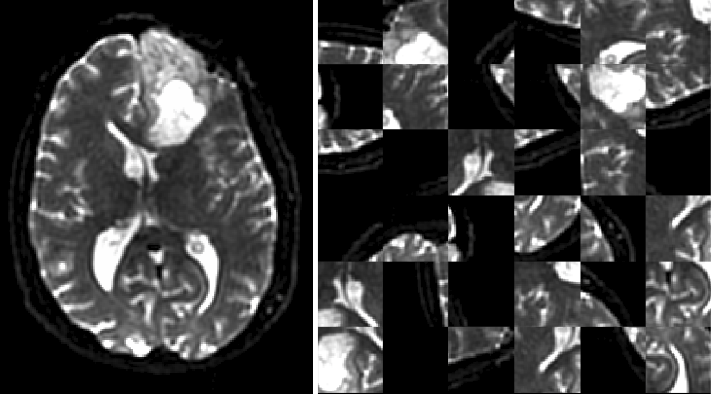

Current Augmentation objects available include 2D and 3D flips and rotations, intensity scaling and shifting, 3D patch extraction, channel-wise dropout, and nearest-neighbor downsampling. Patch extraction can be performed to preferentially select patches that match certain criteria, such as being near a tissue of interest (Figure 4).